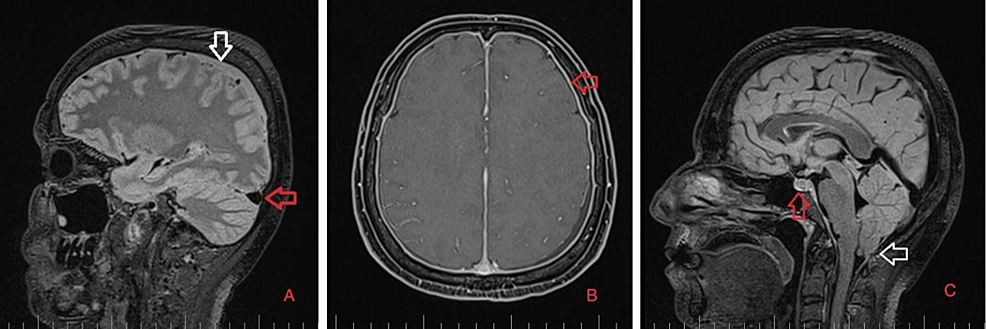

As part of the differential diagnosis, further imaging was performed. A brain MRI on February 1, 2023 (Figure 1) showed the following signs of SIH: subdural fluid collection up to 5.00 mm in the parietal area; diffuse, smooth dural thickening and pachymeningeal contrast enhancement; slightly homogeneous enlargement of the pituitary; cerebellar tonsillar descent into the foramen magnum; distension of the cerebral venous sinuses without thrombosis; and reduced fluid volume in the optic nerve sheath.